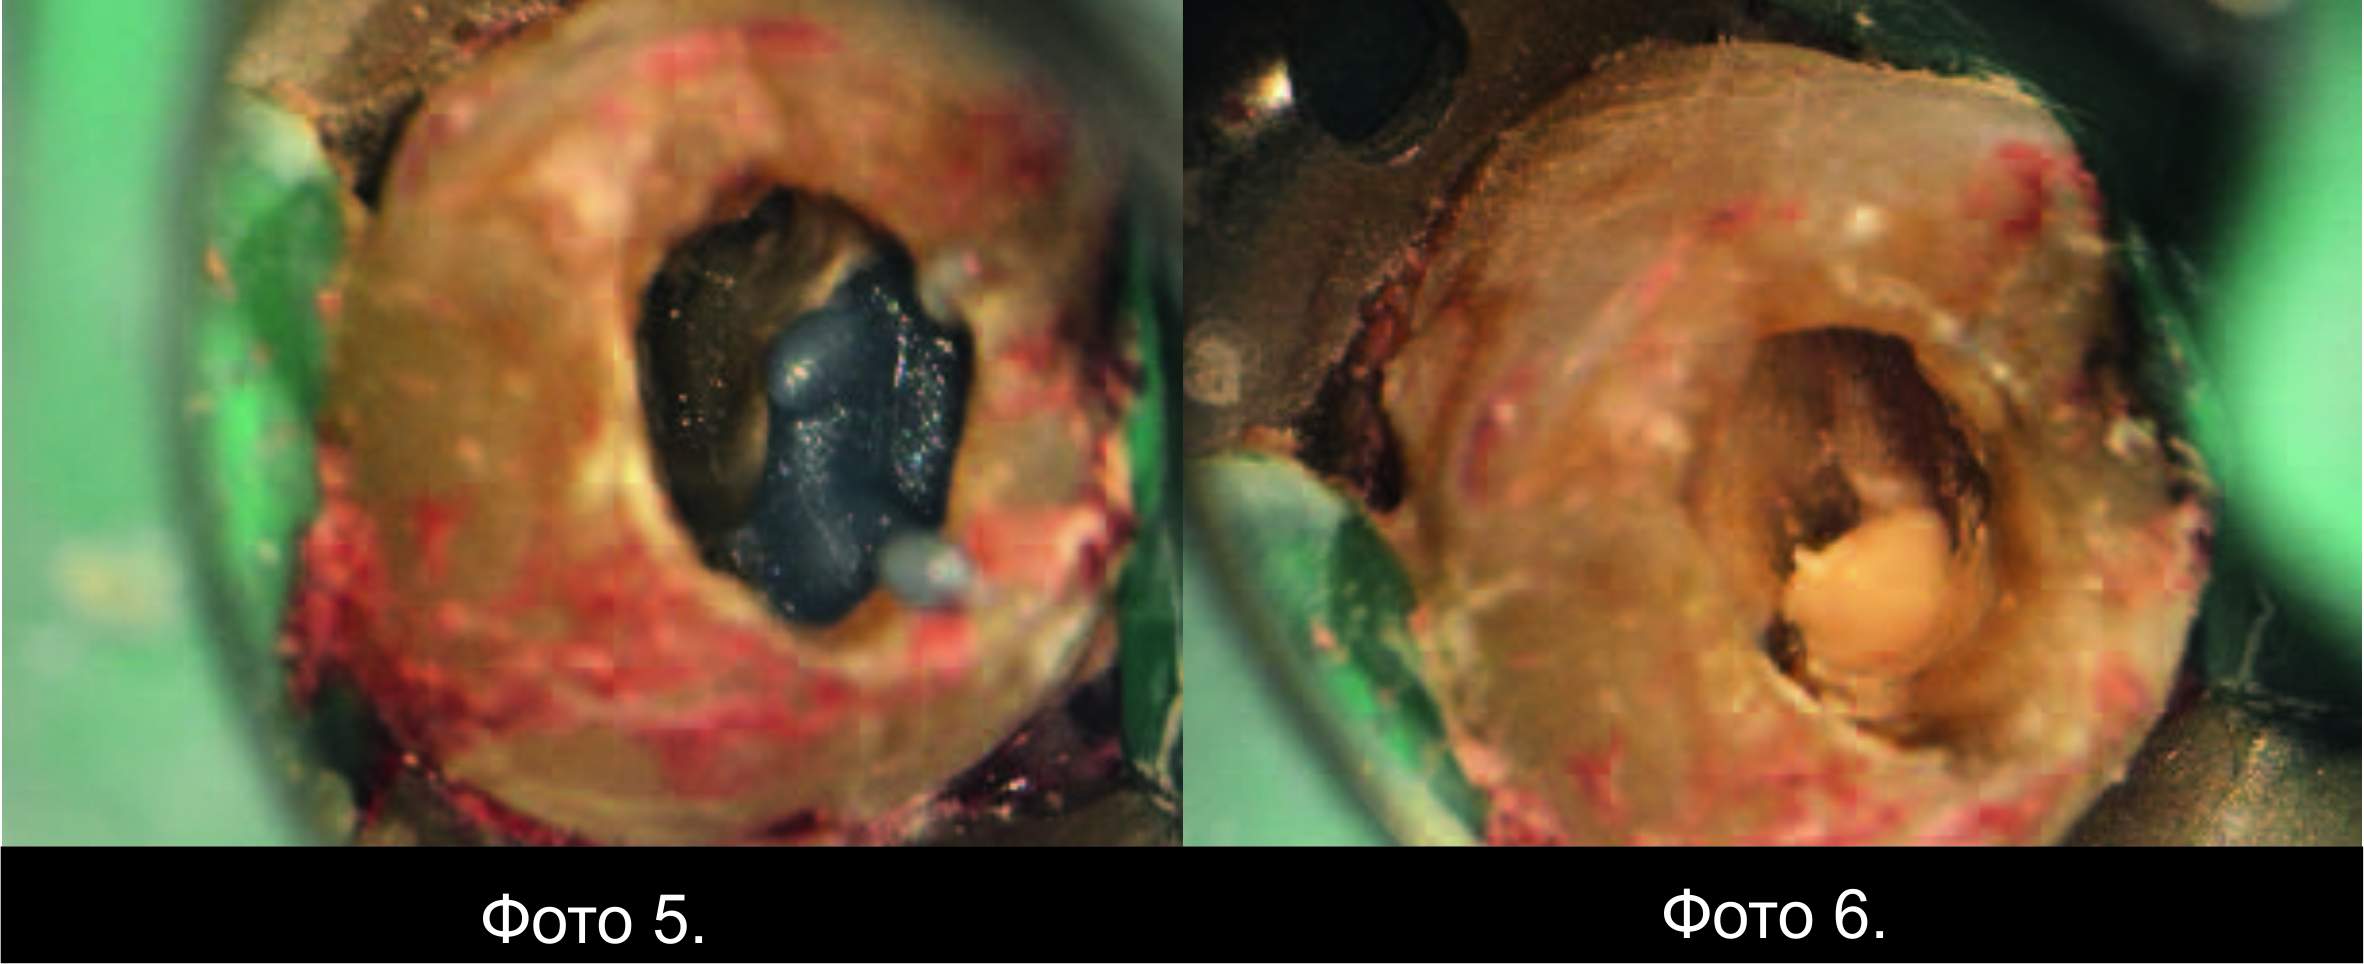

Фото 2 і 3. Перфорація у дистально-піднебінній ділянці.

Кровотеча пародонту була під перфорацією зупинена

гідроксидом кальцію, змішаним із пропіленгліколем. Одразу після цього знайшли

піднебінний канал (Фото 4), і перед тим, як знайти щічні канали, перфорацію

закрили ясенним бар'єром (Фото 5).

Фото 4. Тканину пародонту стабілізовано, піднебінний

канал виявлено.

Фото 5. Перфорацію заблоковано ясенним бар’єром.

Фото 6. Введення Biodentine.